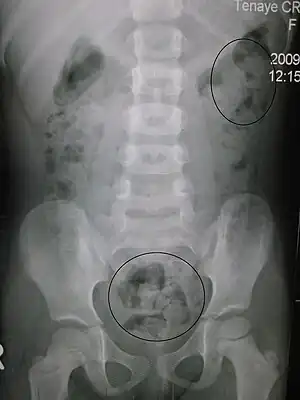

An abdominal x-ray is an x-ray of the abdomen. It is sometimes abbreviated to AXR, or KUB (for kidneys, ureters, and urinary bladder).

KUB is typically used to investigate gastrointestinal conditions such as a bowel obstruction and gallstones, and can detect the presence of kidney stones. The KUB is often used to diagnose constipation as stool can be seen readily. The KUB is also used to assess positioning of indwelling devices such as ureteric stents and nasogastric tubes. KUB is also done as a scout film for other procedures such as barium enemas.